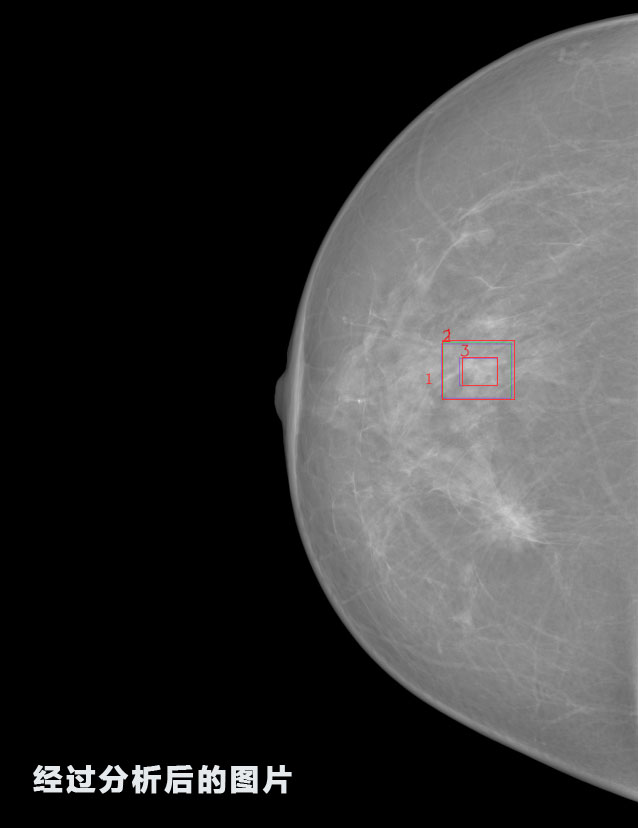

識別報告:

1.發(fā)現良性鈣化,可能性為19.88%---位置框指數:[1796.0867 1359.8237 2058.1372 1582.5334]

2.發(fā)現惡意鈣化的可能性為15.18%---位置框指數:[1789.4733 1365.9951 2063.7698 1576.0613]

3.發(fā)現惡意鈣化的可能性為12.45%---位于框指數:[1859.3987 1422.3184 2006.5494 1528.2698]